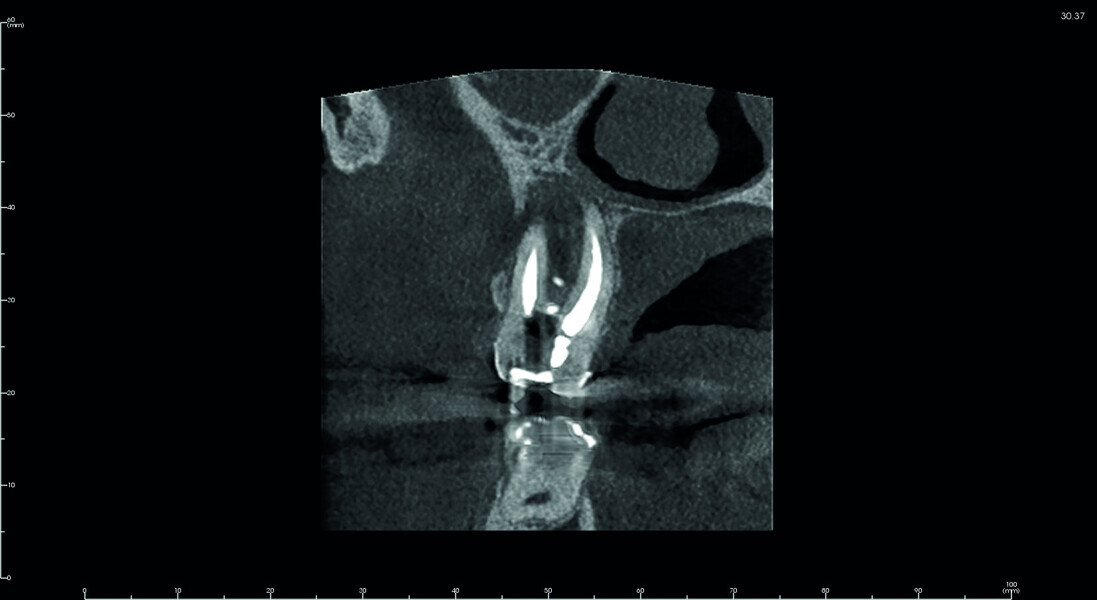

Fig. 6: Pre-op CBCT scan, detailed section of the maxillary second molar.

Fig. 7: Pre-op CBCT scan, coronal and sagittal views.